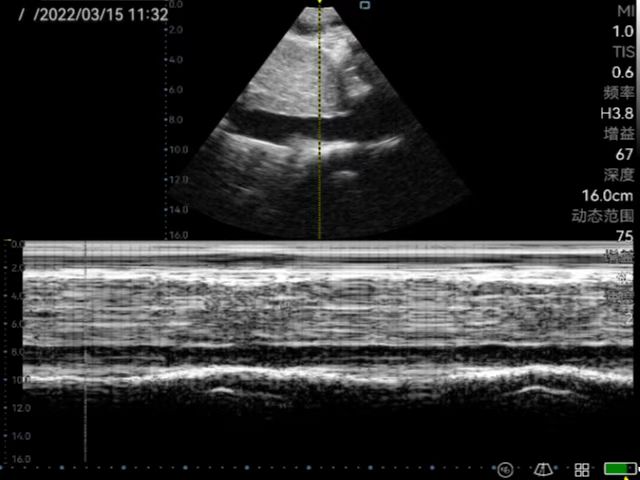

Musculoskeletal ultrasound technology (referred to as musculoskeletal ultrasound) has developed rapidly domestically, and has been continuously promoted and applied in clinical practice. It has become the first choice or gold standard in the diagnosis and treatment of many diseases, such as peripheral nerve diseases, muscle and tendon acute and chronic diseases, early diagnosis and differential diagnosis of rheumatism and rheumatoid diseases. Rehabilitation medicine has developed rapidly in recent years. With the aging of the population, the development of the hierarchical diagnosis and treatment system, and the emergence of precision medicine, medical imaging, especially ultrasound medicine, plays a very important role in rehabilitation medicine. At present, rehabilitation medicine in our country relies on traditional physical examinations, and its blindness, randomness, untargetedness and lack of objective indicators for judging efficacy have attracted more and more attention. Musculoskeletal ultrasound has the advantages of non-invasiveness, convenience and practicality which can be used as the first-choice imaging examination for rehabilitation medicine. Ultrasound positioning and ultrasound-guided puncture injection technology have become the "third eye" of rehabilitation physicians which has an irreplaceable role in manipulative therapy, rehabilitation equipment therapy, injection therapy and sports rehabilitation, etc.

Application in joint ultrasound (wrist, shoulder, elbow, hip, knee, ankle, etc.); Therapeutic application of muscle, tendon, myofascial pain syndrome; Application in urinary system rehabilitation; Application of ultrasound-guided botulinum toxin injection therapy; Applications of Neurosonography; Applications of Cardiac Ultrasound; Application of interventional ultrasound (interventional treatment of joint disease, cystic disease); Expanded application of ultrasound in traditional medicine (ultrasound visualization acupotomy technology); Application of pelvic floor ultrasound in rehabilitation of diseases; Application of ultrasound-guided puncture in pain.